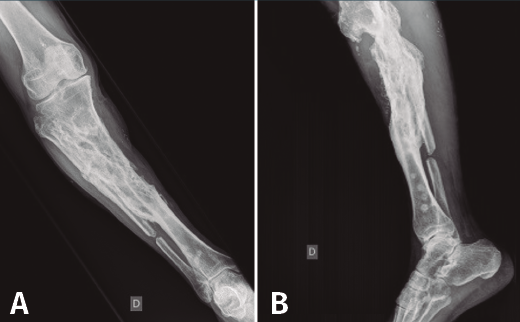

Figura 4. Radiografías de frente y de perfil de tibia-peroné donde se objetiva la resección ósea realizada.

En el estudio radiológico posquirúrgico (Figura 4) se puede objetivar la resección ósea realizada.